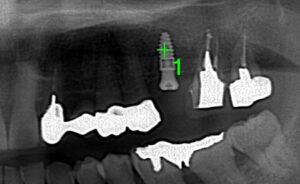

ソケットリフトの術式です。この場合はインプラントの

周囲の骨の幅は十分にありましたので外側内側に

人工骨を補填する必要がないため、フラップレスといい

歯茎に切開を加えずパンチでインプラントの穴を

開けました。非常に低侵襲な処置になります。

8mmのインプラントを埋入するのですが

骨が7mmのためドリルで6mmまで削り超音波装置で

粘膜を破らず骨だけに穴を開け、画像に出ています

オステオトームという器具を槌打(ついだ)して上顎洞粘膜を

挙上させます。

インプラントを埋入を終えキャップを装着した

ところです。切開、縫合をしていませんので

術後も痛々しくありません。

レントゲン画像です。必ずCTで確認をします。